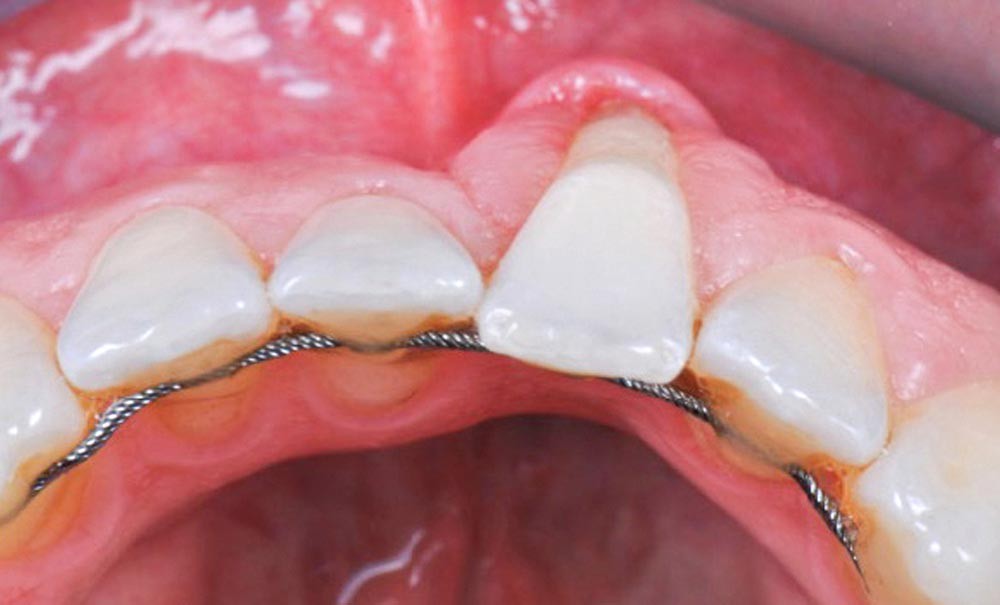

Certaines complications peuvent apparaître suite à la pose de ces contentions fixes, notamment « le syndrome du fil ». Il est décrit par le Dr Florence Roussarie [4/5] comme une complication inattendue, plus ou moins sévère, suivant un traitement orthodontique, qui correspond à des mouvements parasites du secteur incisivo-canin bien que les dents semblent parfaitement collées à un fil de contention. Des espaces entre les dents peuvent apparaître ainsi que des modifications de l’inclinaison entraînant les dents en dehors des bases osseuses. Ces mouvements inattendus d’inclinaison des dents peuvent être accompagnés de récessions gingivales plus ou moins sévères nécessitant souvent une greffe gingivale [6].

Ces mouvements indésirables sont retrouvés principalement à la mandibule [7], la contention maxillaire fixe collée étant moins fréquente. De plus, l’impact esthétique de l’apparition d’un torque différentiel au maxillaire amène le patient à consulter plus précocement.

Certains auteurs, tels que Pazera [8], décrivent dans une étude de cas une complication à la suite de la pose d’un fil torsadé souple, collé sur les faces linguales des six dents antérieures mandibulaires. Quatre ans après un traitement orthodontique, il observe l’apparition d’une inclinaison radiculo-vestibulaire de 35° sur une canine mandibulaire. Katsaros, pour sa part, a décrit des mouvements…